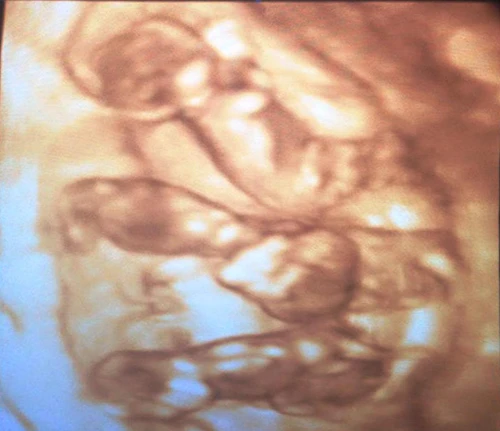

Hình ảnh siêu âm thai nhi của sản phụ Xuân. Ảnh:Quang Hà.